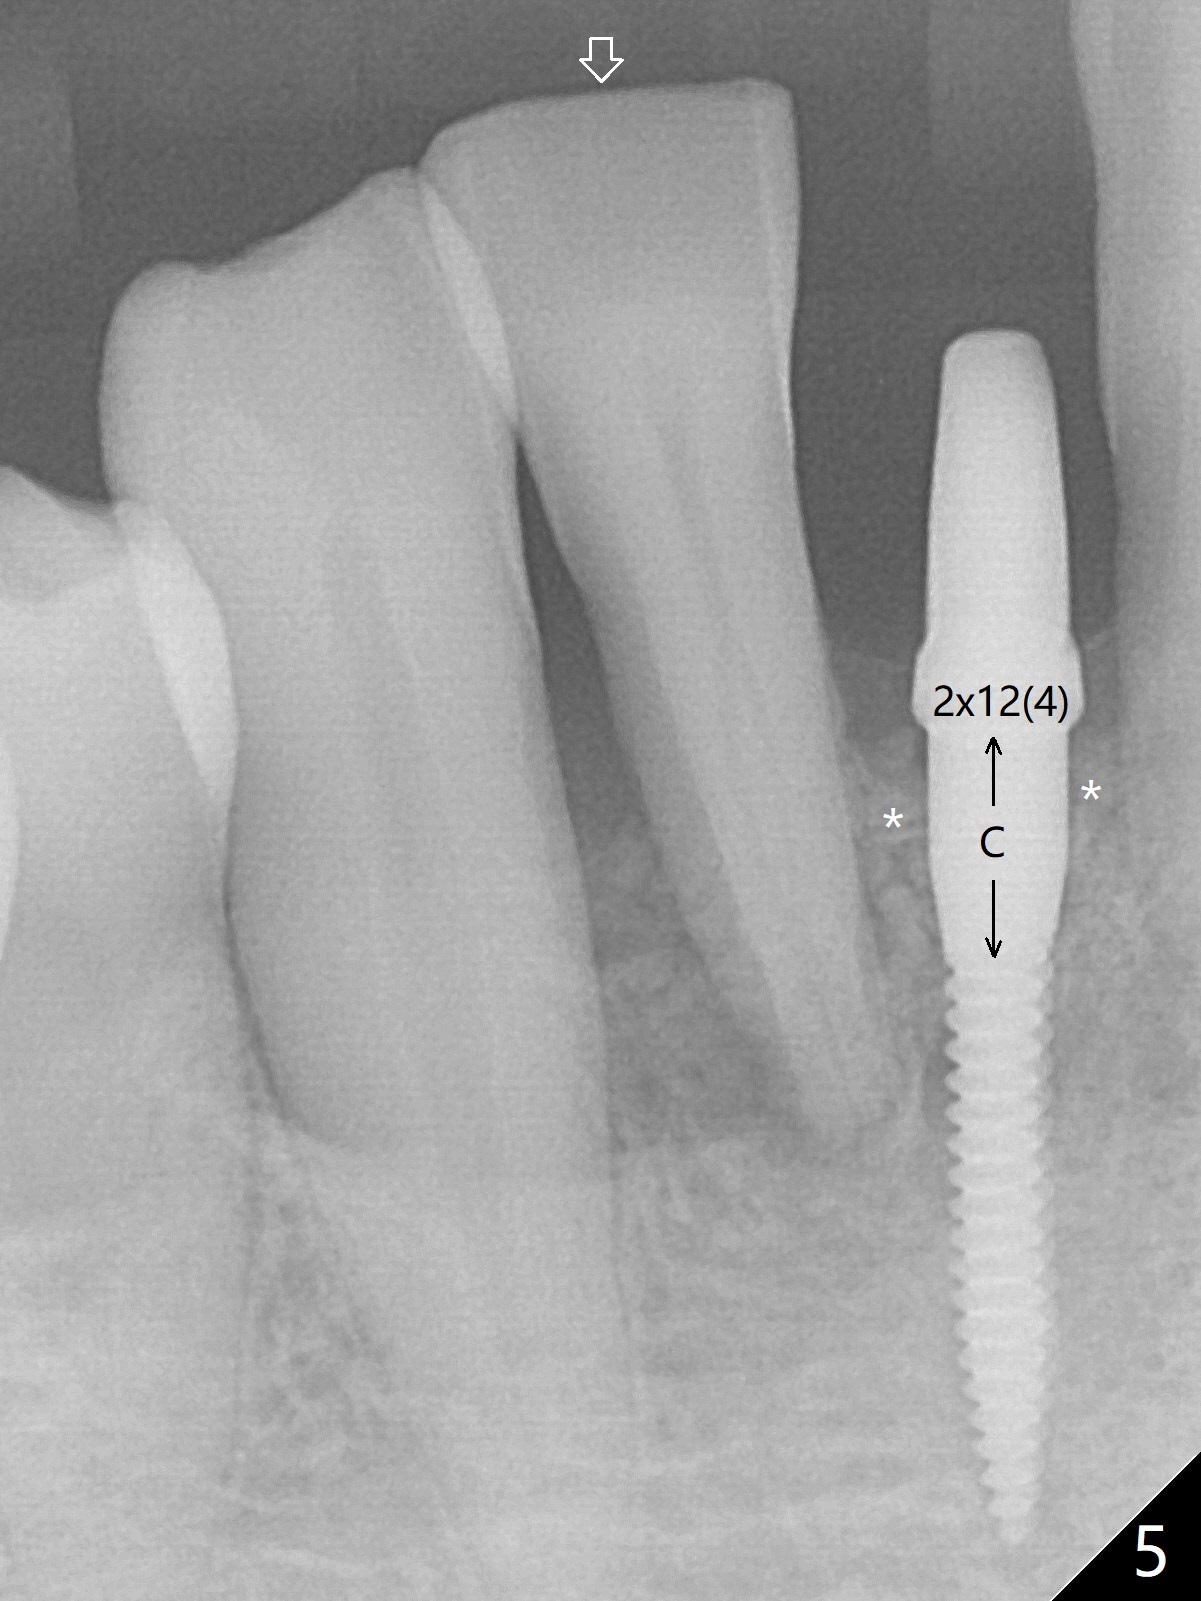

Out of financial concern, the patient does not agree to have the tooth #26 extracted. Due to atrophy of the most coronal ridge buccally at #25 (Fig.1,2 *), osteotomy is initiated difficult and distal (Fig.3). After 1.2 mm drill removal (Fig.3' black area), Lindamann bur is used to move the osteotomy mesial (red area). A 2x12(4) mm 1-piece implant is placed (Fig.4,5); the buccal defect is packed with allograft (Vanilla, .5-1 mm cancellous/cortical mixture, *). When the tooth #26 fails, a 2 mm implant will be placed (Fig.6 blue). Following abutment adjustment, a provisional is fabricated (Fig.7 P); note the lower incisal edges of #25 and 26, as compared to those of the neighboring teeth. To reduce occlusal trauma, the incisal edge of the tooth #26 has been decreased (Fig.5 open arrow). The implant threads seem not to be exposed 4 months postop (Fig.8), although the tooth #26 has mobility II.